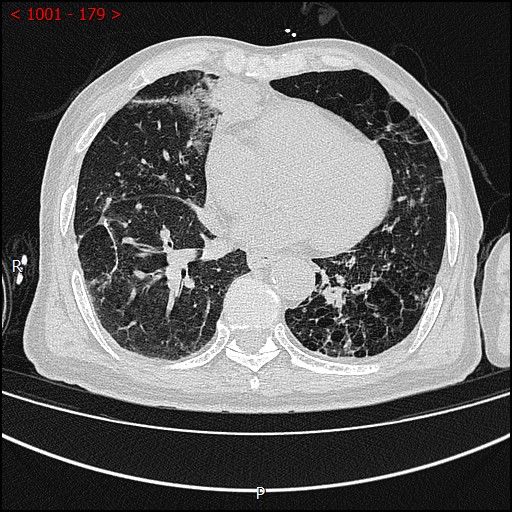

术中影像

男性患者,68岁,检查发现右肺中叶肿块,大小约3.5cm×2.4cm,因患者有慢性支气管炎、肺气肿、肺大泡,基础病较多,无法耐受常规外科手术治疗;经与患者本人及家属多次沟通。血管介入科团队根据患者具体情况决定对该患者施行CT引导下肺肿瘤射频消融术。经全科术前讨论:肿瘤位置毗邻心脏、纵膈、胸膜多处重要器官,手术要求穿刺精准,消融位置精确,尽量避免恶性心率失常,心脏包膜、胸膜、纵膈损伤。经过前期的精心术前准备,2023年7月18日,在血管介入科团队和CT室默契配合下,此次射频消融手术顺利完成。手术全过程仅用时约40分钟,其中消融时间约5分钟。CT观察下见肿瘤形变,周围肺组织呈现“晕”征,提示本次消融范围基本覆盖全肿瘤。术中患者无疼痛并且未产生并发症。本次手术达到杀死肿瘤细胞的同时,最大限度的减少创伤、保留肺组织。